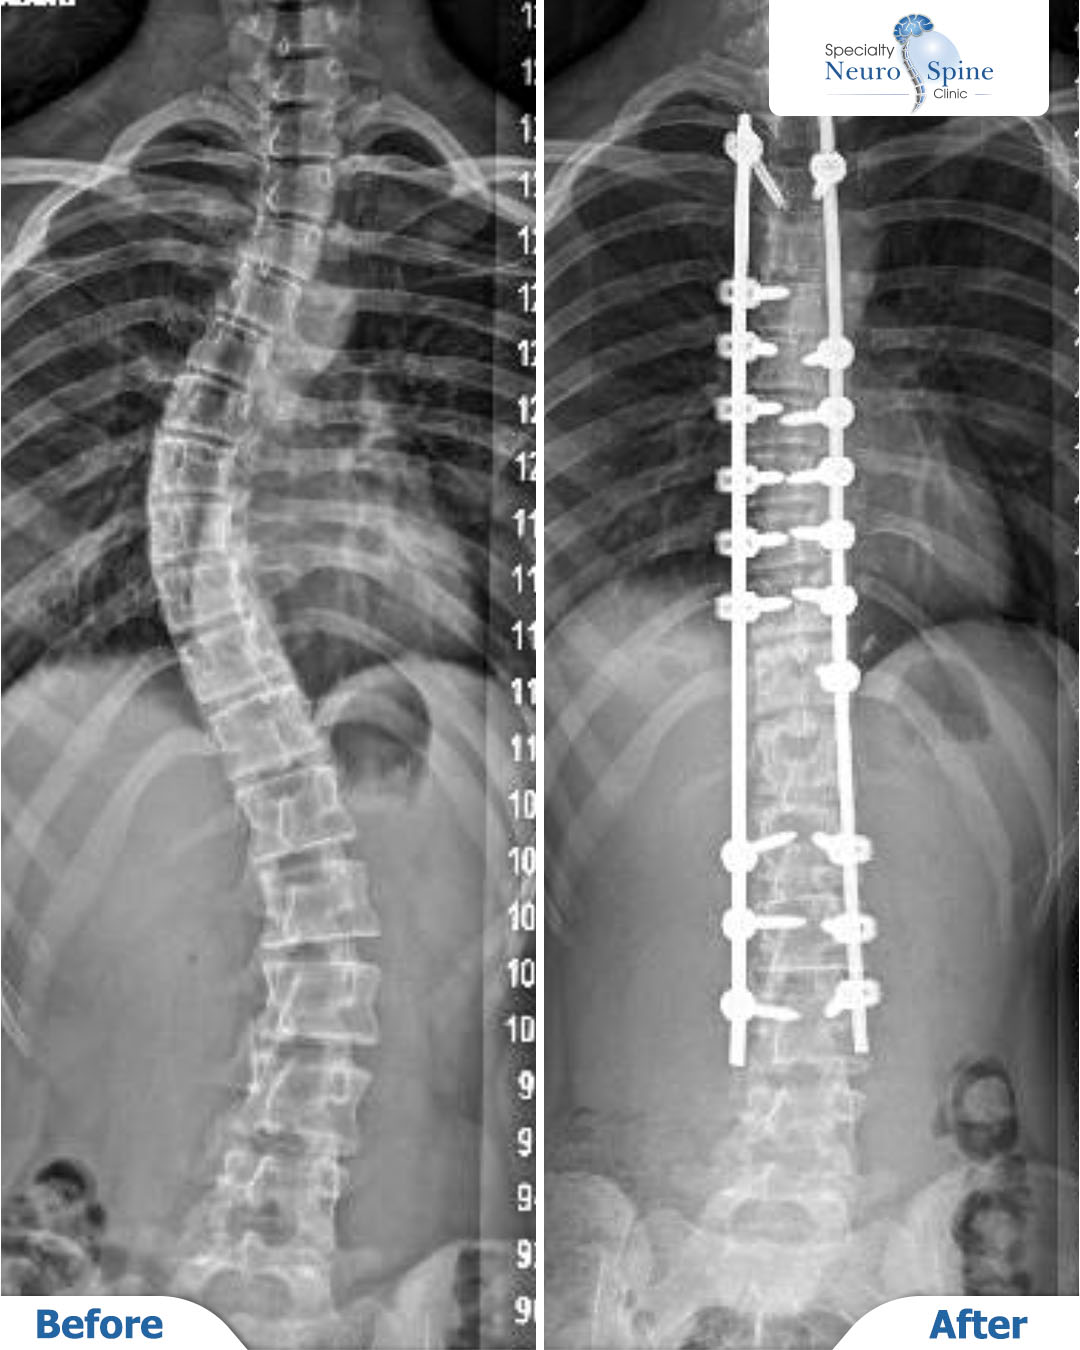

قبل وبعد صور الأشعة لمريضتنا العزيزة مريم، البالغة من العمر 14 عامًا، من روسيا، التي خضعت لعملية تثبيت العمود الفقري بالتداخل الجراحي المحدود من الفقرة الصدرية الثالثة حتى القطنية الثالثة.